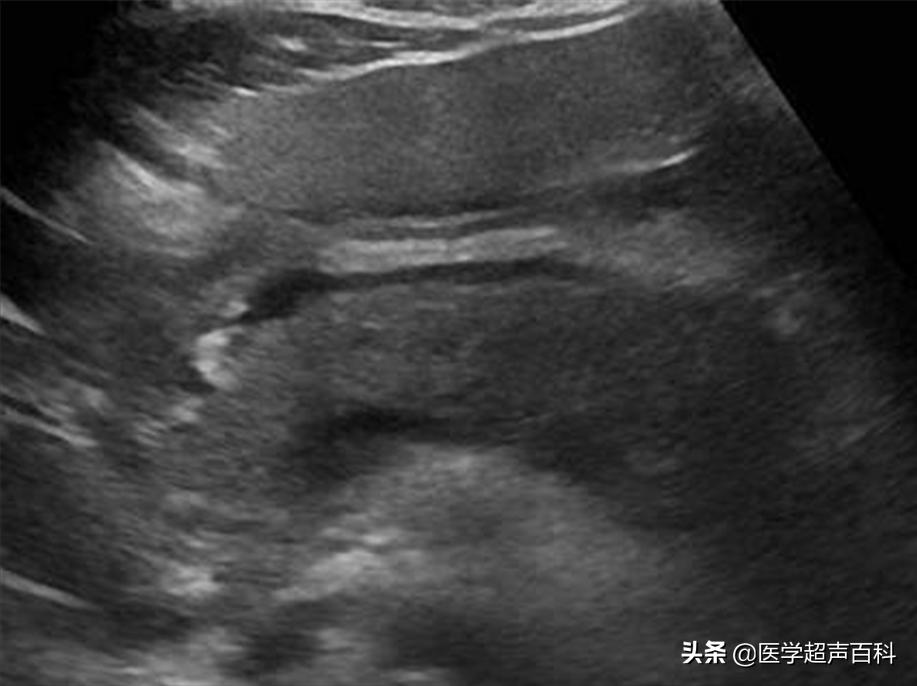

水肿型胰腺炎:胰腺弥漫性增大,边缘形态规整,内部回声减低,胰腺后方血管受压迫显示不清

急性胰腺炎声像图表现

(1)胰腺弥漫性或局限性增大,可失去正常形态,轮廓不清。

(2)内回声减低,呈弥漫分布的弱点状,中间有强弱不均、形态不整、边界不清的片状回声。严重水肿时呈透声暗区,似囊肿声像图。

(3)多伴胰腺区胃肠气体增多,以胰头区更甚,使探查更为困难。